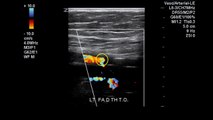

MRI CT MAGNETIC RESONANCE IMAGING NORMAL ANATOMY.\r<br>\r<br>Color and pulsed Doppler as well as gray-scale imaging demonstrated normal blood flow in both kidneys. Acceleration times demonstrated normal renal arterial .\r<br>\r<br>\r<br>\r<br>Trying to locate the origin of the renal artery with ultrasound can slip you up. but dont go bananas! This handy hot tip shows how to look for the Banana Peel .\r<br>\r<br>Disclaimer: The medical information contained herein is intended for physician medical licensing exam review purposes only, and are not intended for diagnosis .